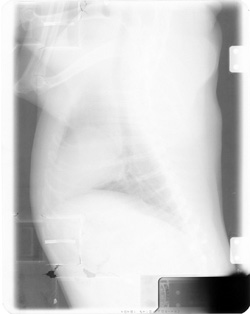

Upside Down Cassettes